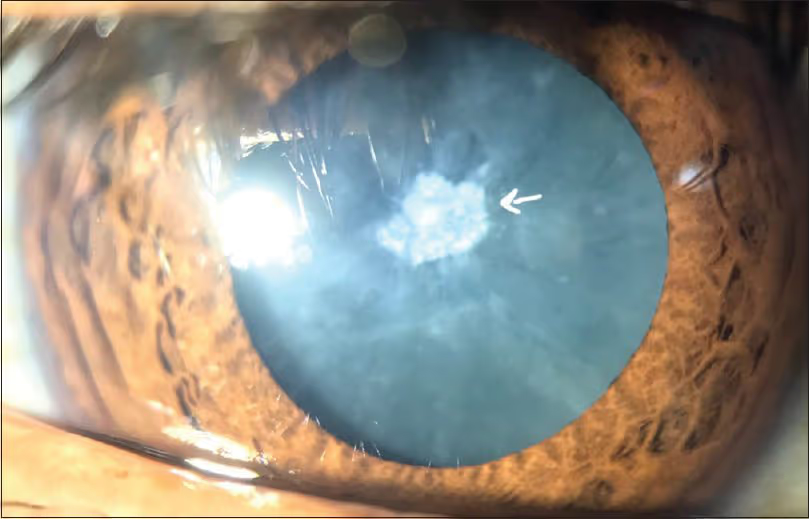

Tipos de catarata

- Catarata secundária: consequência de outra doença ou condição, como diabetes, uveíte e miopia alta.

- Catarata cortisônica: subtipo da secundária, causada por uso prolongado de corticoides.

- Uveíte: inflamação intraocular que pode levar à catarata secundária.

- Uso prolongado de corticoides (orais, tópicos ou inalatórios).